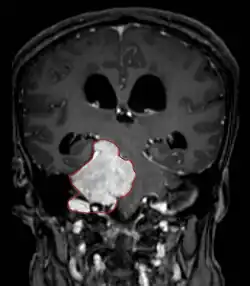

• CT

• Well-defined extra-axial mass that displaces normal brain. Smooth in contour, sometimes calcified

• About 60% hyperdense with normal brain without contrast

• About 70% brightly and homogenously enhance with contrast (less frequent in malignant or cystic meningiomas)

• MRI

• Preferred imaging because it can show dural origin

• Dural tail sign seen in about two-thirds: characteristic marginal thickening that tapers peripherally along the dura

• Isointense on T1, hyperintense (usually homogeneously) on T2, strong enhancement with IV contrast